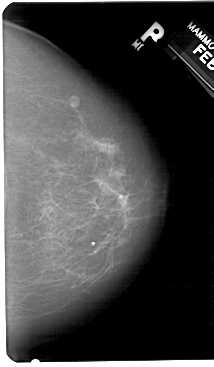

A_1278_1.RIGHT_CC

RIGHT_CC LINES 5491 PIXELS_PER_LINE 3196 BITS_PER_PIXEL 12 RESOLUTION 43.5 NON_OVERLAY